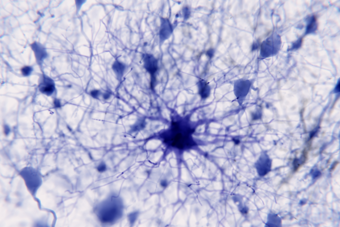

We’re seeking greater understanding of the genetics and pathophysiology of diseases of the brain and nervous system, and improving the diagnosis and surgical, medical and psychological management of neurological disease, intellectual disability and cognitive health.

Glial Neurobiology, Cognition and Behaviour Research